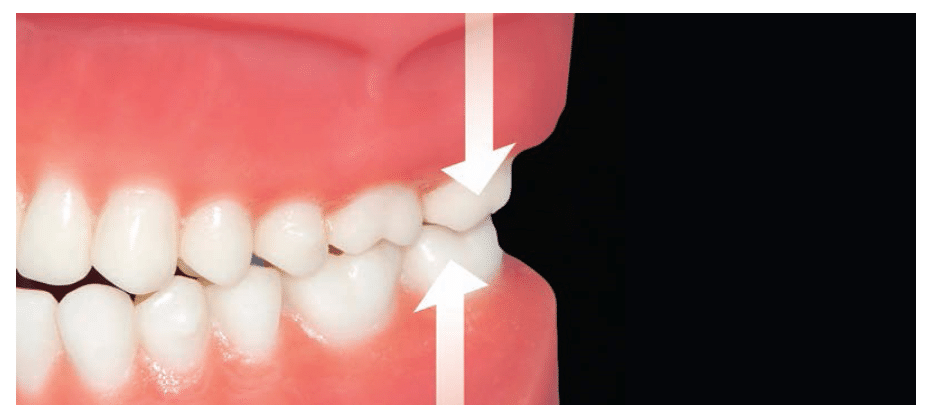

사진처럼 씹는 힘이 강하거나 이를 꽉 무는 습관이 있는 경우, 인레이가 망가질 확률이 올라갑니다(출처: https://dimensionsofdentalhygiene.com)

특히

어금니 부위 인레이는

교합력(씹는 힘)을 직접 받기 때문에

인레이 내구성에 더 큰 영향을 받아요.